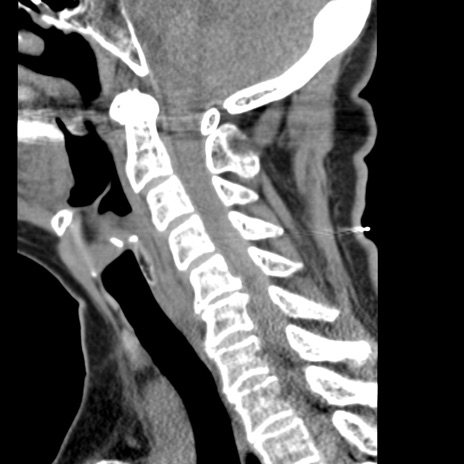

症例50 頚椎CT(矢状断像)

頚椎CT

冠状断像